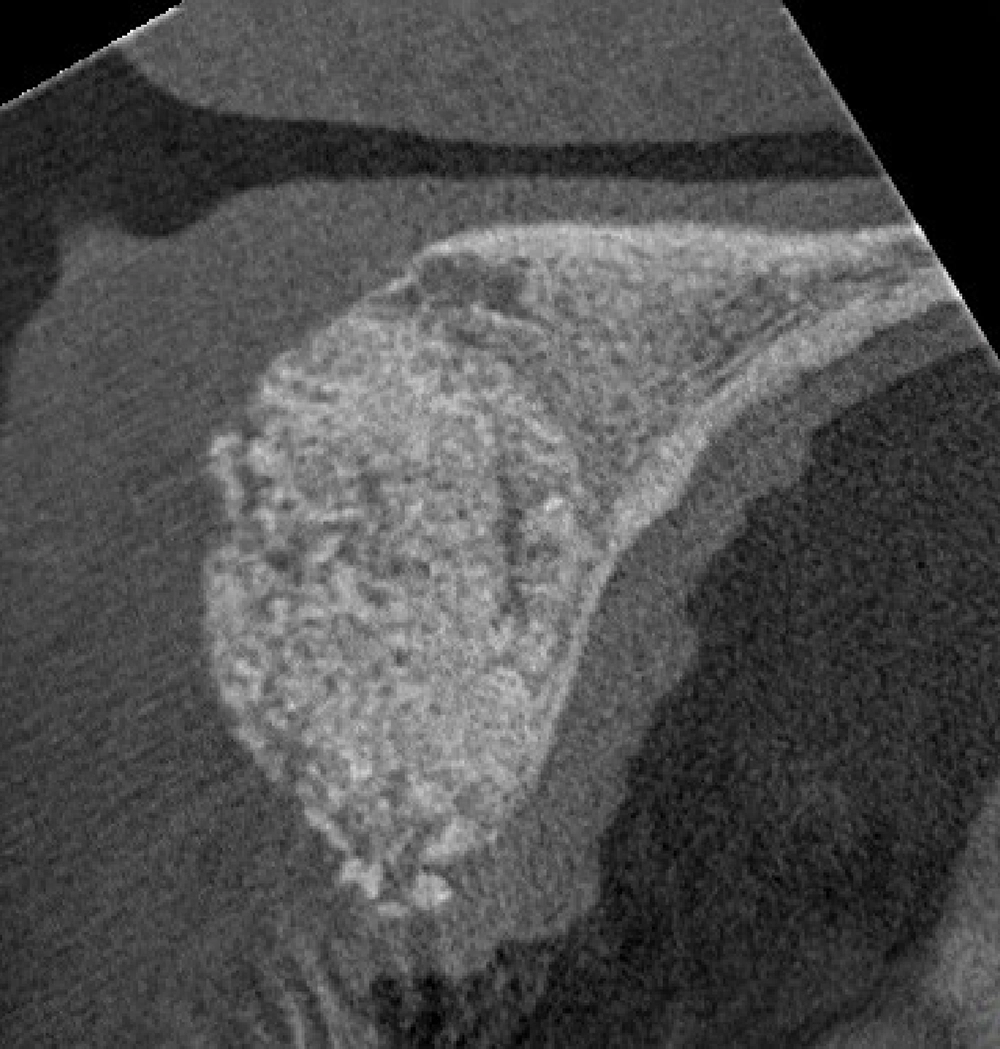

Hard Tissue Augmentation

Restores lost bone in areas where dental implants are planned. Bone grafts—either natural or synthetic—are used to rebuild the alveolar bone for strength and stability

Hard tissue augmentation 3 (a)